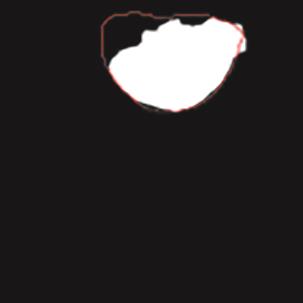

乳腺癌是全球女性最常见的恶性肿瘤之一,准确的病变分割对于乳腺癌的早期诊断与治疗具有重要意义。然而,由于病变形态的多样性以及超声成像机制的复杂性,现有基于深度学习的乳腺超声图像病变分割方法在分割准确性方面仍面临巨大挑战。为进一步提升乳腺超声图像中病变区域的分割精度,该文基于经典U-Net架构,提出了一种新型乳腺超声图像病变分割网络(CWSASKM-BBAM-Net)。首先,在网络中引入逐通道空间自适应选择核卷积模块(CWSASKM),根据不同通道的语义特征为每个空间位置自适应选择感受野大小,以增强多尺度信息的建模能力;然后,引入双向边界感知机制(BBAM),通过融合正向与反向注意力,对目标显著区域及其边界进行协同建模,同时逐步提升对非显著区域与病变区域的区分能力,以进一步强化边界信息的表达;最后,在3组公开乳腺超声图像数据集(BUSI、UDIAT和STU)上开展分割实验。结果表明:该方法在数据集BUSI上的杰卡德指数、精确率、召回率和Dice相似系数分别为71.97%、82.85%、81.40%和80.44%,较次优方法分别提升1.69、1.05、1.28和1.84个百分点;在数据集UDIAT上,这4项指标分别达到78.14%、88.31%、86.73%和86.10%,较次优方法分别提升了2.75、2.04、0.56和2.01个百分点;在外部数据集STU上,该方法也取得了优于其他方法的整体表现。实验结果表明,CWSASKM-BBAM-Net在乳腺超声图像分割任务中展现出更优的整体性能。